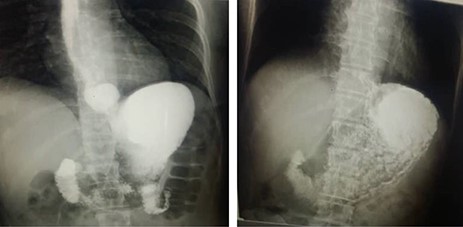

A hiatus hernia (HH) occurs when the viscera of the abdomen protrude through the oesophageal hiatus to the thoracic cavity [1]. HH is not commonly seen among the paediatric age group, and it is asymptomatic most of the time. However, it may vary in symptoms and complications [2], with regurgitation being the most common in the first year of life [3]. In this case series report, we describe four siblings (see Fig. 1) who had HH with their lower oesophageal sphincter (LES) locating above the diaphragm. They were born from a father with gastro-oesophageal reflux disease (GORD) without HH and the mother with asymptomatic HH with reflux (see Fig. 2). The parents were fourth-degree-related. Three of the children had symptomatic sliding diaphragmatic HH with uncommon presentations and the other child with a more advanced hernia. The patients did not have pulmonary hypoplasia, and there was a positive history in two siblings of the father (out of five) who had small symptomatic hiatus hernia and a negative history from the mother. The parents had four affected children in addition to one child who died from pneumonia at 2 years of age.

Parents’ barium swallow: (1) It shows on the left the asymptomatic hiatus hernia of the mother with reflux. (2) It shows on the right a reflux with the father who was symptomatic with no hernia.